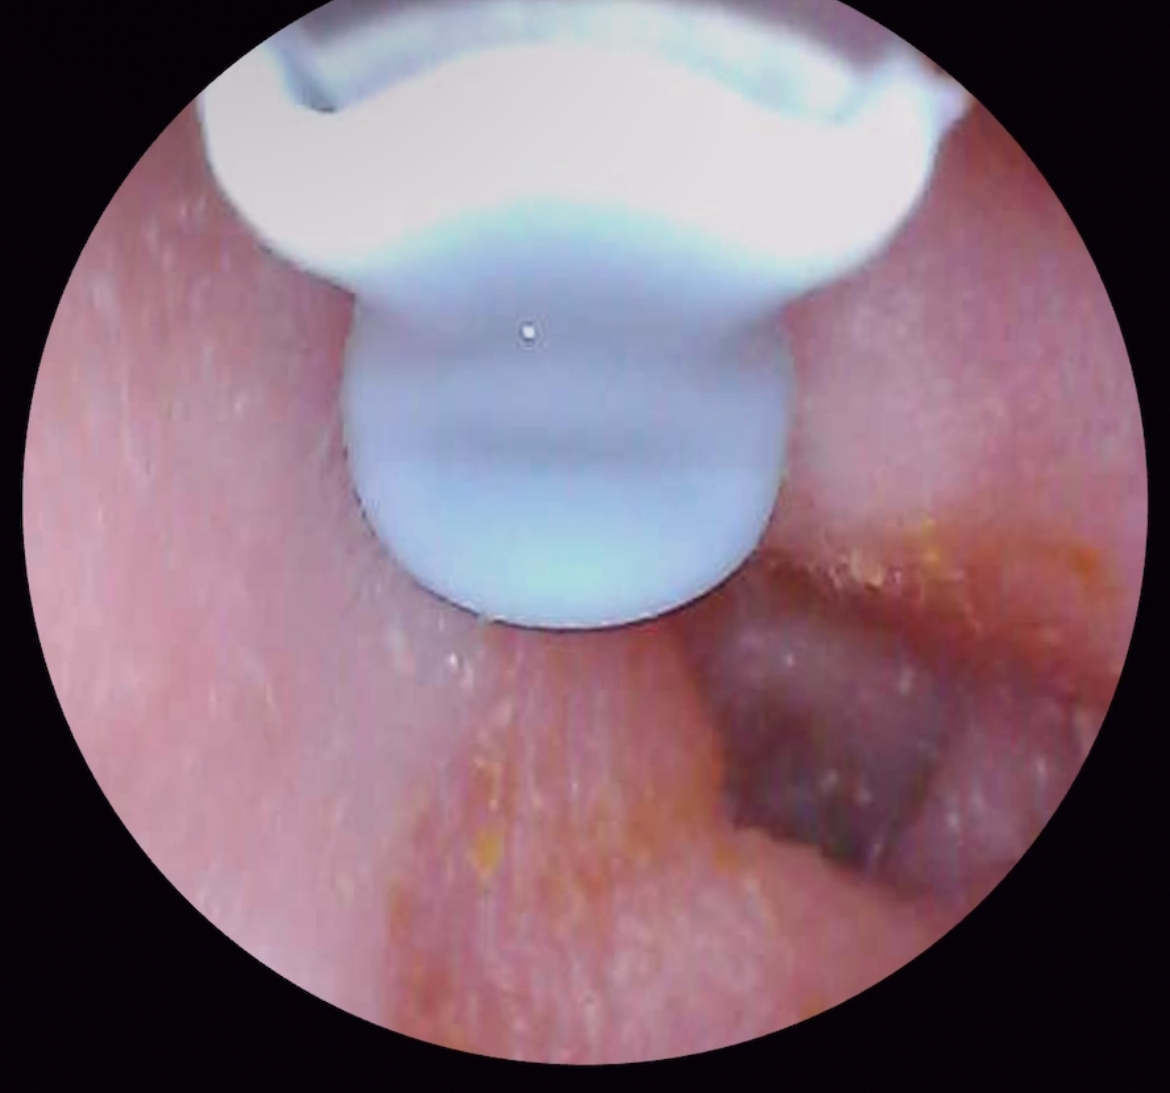

неужели надули ушко? Из 1 ушка заметила засохшее уже, видимо что то желтое вытекало

Чанга,я могу ошибаться ,но кажется воспаление есть.Сверьте в гугле норму и воспаленнок ухо . Решайте сами . Сходите к лор или если нет лора рядом , воспользуйтесь онлайн приемной. Я не пользовалась сама , но блогер рекламировал приложение « напоправку» там все врачи онлайн консультируют